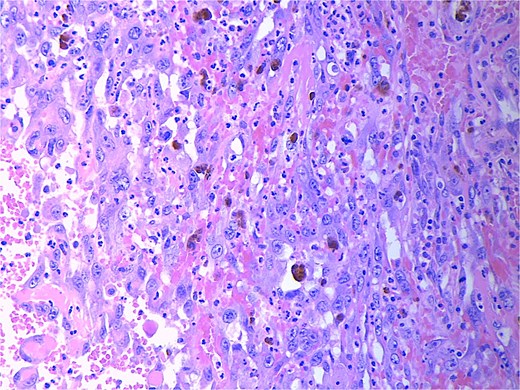

Final pathology revealed an angiosarcoma of the adrenal gland. Sections showed a predominantly hemorrhagic and necrotic mass with residual vascular forming channels within the adrenal gland (Fig. 2). Cells were pleomorphic spindled to epithelioid and atypical (Figs 3 and 4), with a mitotic count of 12/10 high-power fields. Immunohistochemistry showed positivity for ERG (Fig. 5), CD34, and focal pankeratin and negativity for SF-1, SOX10, Cathepsin-K, and chromogranin. There was no lymphatic or vascular invasion identified, and the margins were uninvolved by the tumor. The left kidney was negative for tumor, and the background adrenocortical parenchyma was benign.

High power magnification (20×) H&E showing malignant cells forming vascular channels with atypia and multiple mitotic figures.

High power magnification (40×) H&E showing malignant cells forming vascular channels with atypia.